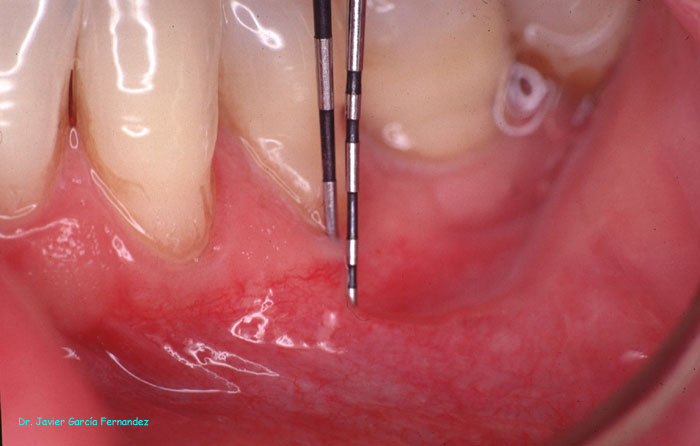

Atlas of Surgical Techniques in Periodontics. Chapter I. Diagnostic of Peridontal Diseases. Classification. Atlas de Técnicas Quirúrgicas en Periodoncia. Cap. I. Exploración y Diagnóstico. Atlas de Técnicas Quirúrgicas en Periodoncia

image171